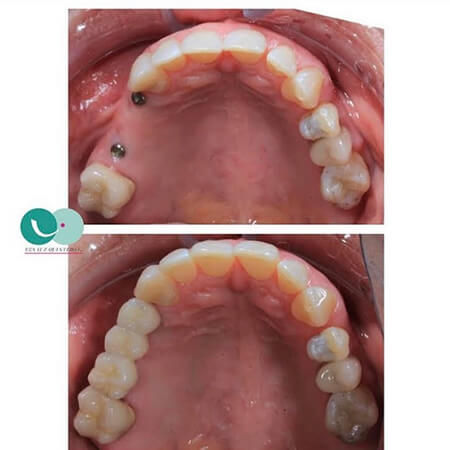

Before and After Gallery

- Rehabilitation on dental implants, hybrid prostheses, Seniors Ilapeo Curitiba, Brasil 2018

Estoy completamente felizzzz , me realizaron implantes con coronas de Zirconio y láminas en cerámica en los dientes de adelante superiores y tuvo el mejor cuidado para complementar el color de mi dentadura de manera muy perfecta , la felicidad es toda , demasiado profesional y ética , estoy completamente feliz , Me hizo otros tratamientos donde implicaba mucho tiempo y la constancia y dedicación me sorprendió y lo logró en el menor tiempo posible , es sorprendente su empatía con el paciente, muchas gracias Doctora Eva